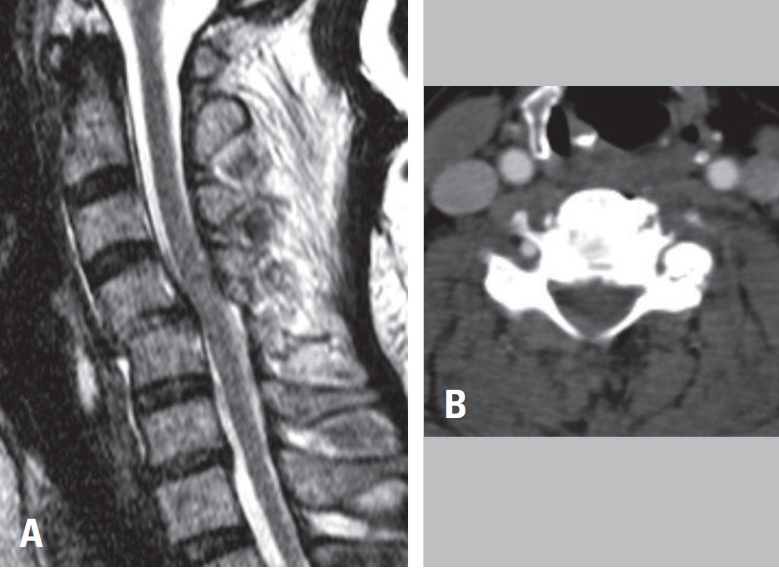

60-year-old woman presented following a motor vehicle collision with notable upper extremity weakness. On examination, motor strength was 2/5 in the left arm and 3/5 in the right arm. Cervical spine radiographs revealed dislocation at the C4–C5 level (

Fig. 1A). Computed tomography demonstrated locking of the left facet joint and subluxation of the right facet joint (

Fig. 1B). Magnetic resonance imaging showed spinal cord compression at C4–C5 with corresponding intramedullary signal change (

Fig. 1C).

To evaluate for vertebral artery injury secondary to facet dislocation, neck CT angiography was performed, confirming occlusion of the left vertebral artery at C4–C5 (

Fig. 1.

(A) Lateral cervical spine radiograph demonstrating traumatic anterior translation at C4–C5. (B) Cervical spine CT showing left C4–C5 facet dislocation. (C) Cervical spine MRI revealing spinal cord signal change at the C4–C5 level. (D) Neck CT angiography demonstrating occlusion of the left vertebral artery at C4–C5 secondary to facet dislocation.